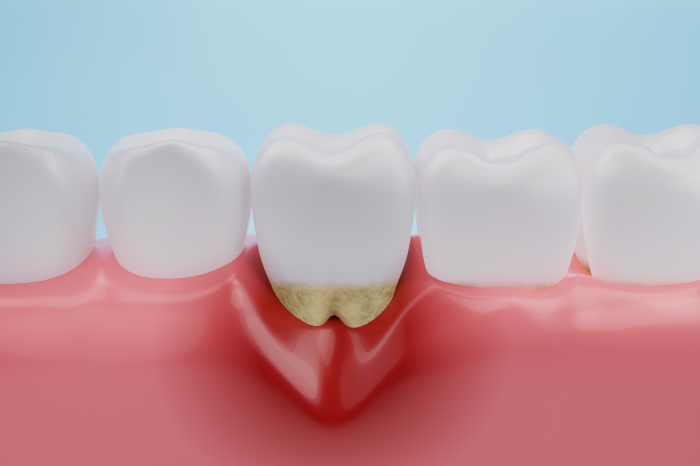

치아와 잇몸 틈새에 쌓인 치석은

잇몸 속 치주낭까지 파고들어

치주낭 속에 쌓이게 되는데요.

이렇게 잇몸 속에 쌓인 치석을

흔히 치은연하라고 부르는데요.

치은연하는 잇몸 속에 자리 잡은 치석이라

양치질만으로는 제거하기가 어려워

오랜 기간 방치될 수밖에 없습니다.